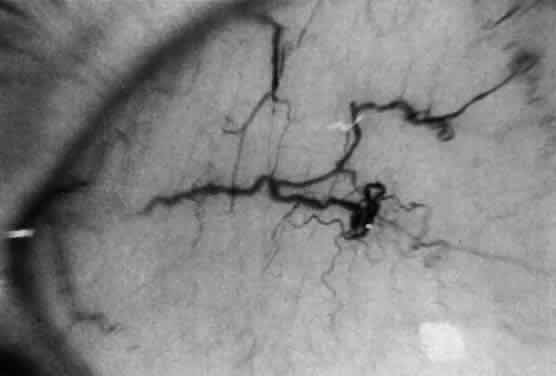

A unique retinal abnormality, the macular halo syndrome, has been reported in type B NPD by Cogan and Kuwabara135 and consists of a ring of opacities around the macula that causes no visual impairment (Fig. 15). This abnormality has been reported by several authors.141–143The crystalloid halo which measures about half the disc diameter occurs at the outer edge of the retina mainly in Henle's fiber layer causing only minor obstruction of the overlying vessels. Matthews and associates144 proposed that the macular halo represents the mildest form of a cherry-red spot in the ganglion cell layer of the retina. Their findings are in conflict with those of Cogan et al.138 The precise location of the opacities in the retina remains uncertain because of the lack of histopathology. The available clinical data suggest that such opacities are permanent.

Fig. 15. Macular halo in a patient with Niemann-Pick type B.